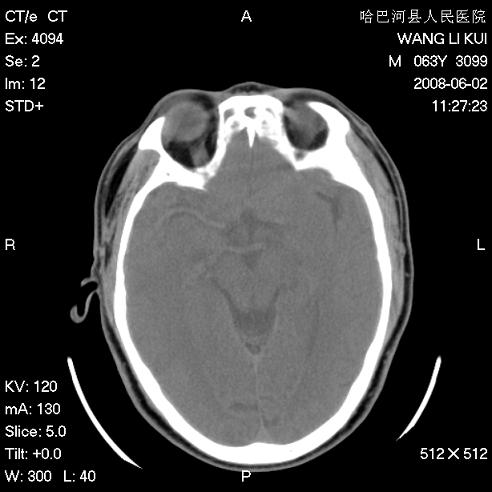

标题: CT13803:反复性鼻塞、流涕一年余 [打印本页]

标题: CT13803:反复性鼻塞、流涕一年余

1.全组副鼻窦炎2.双侧上颌窦积液

.全组副鼻窦炎2.双侧上颌窦积液

1)全副鼻窦炎(左侧上颌窦黏膜下囊肿或息肉)。2)左眼眶肌锥内不规则小结节状软组织密度影;考虑为小血管瘤可能。建议行ct增强扫描检查。

全组副鼻窦炎,左侧肌锥内不规则形软组织肿块影,与眼外肌密度相当,左侧视神经受压,肿块与视神经及眼外肌分界清晰,眼外肌无增粗,眶壁无破坏,球后脂肪间隙不模糊,考虑良性改变,小血管瘤或神经源性肿瘤可能,建议增强扫描。

谢谢,增强扫描做了,眶内病灶与海绵窦同步明显强化,血管瘤